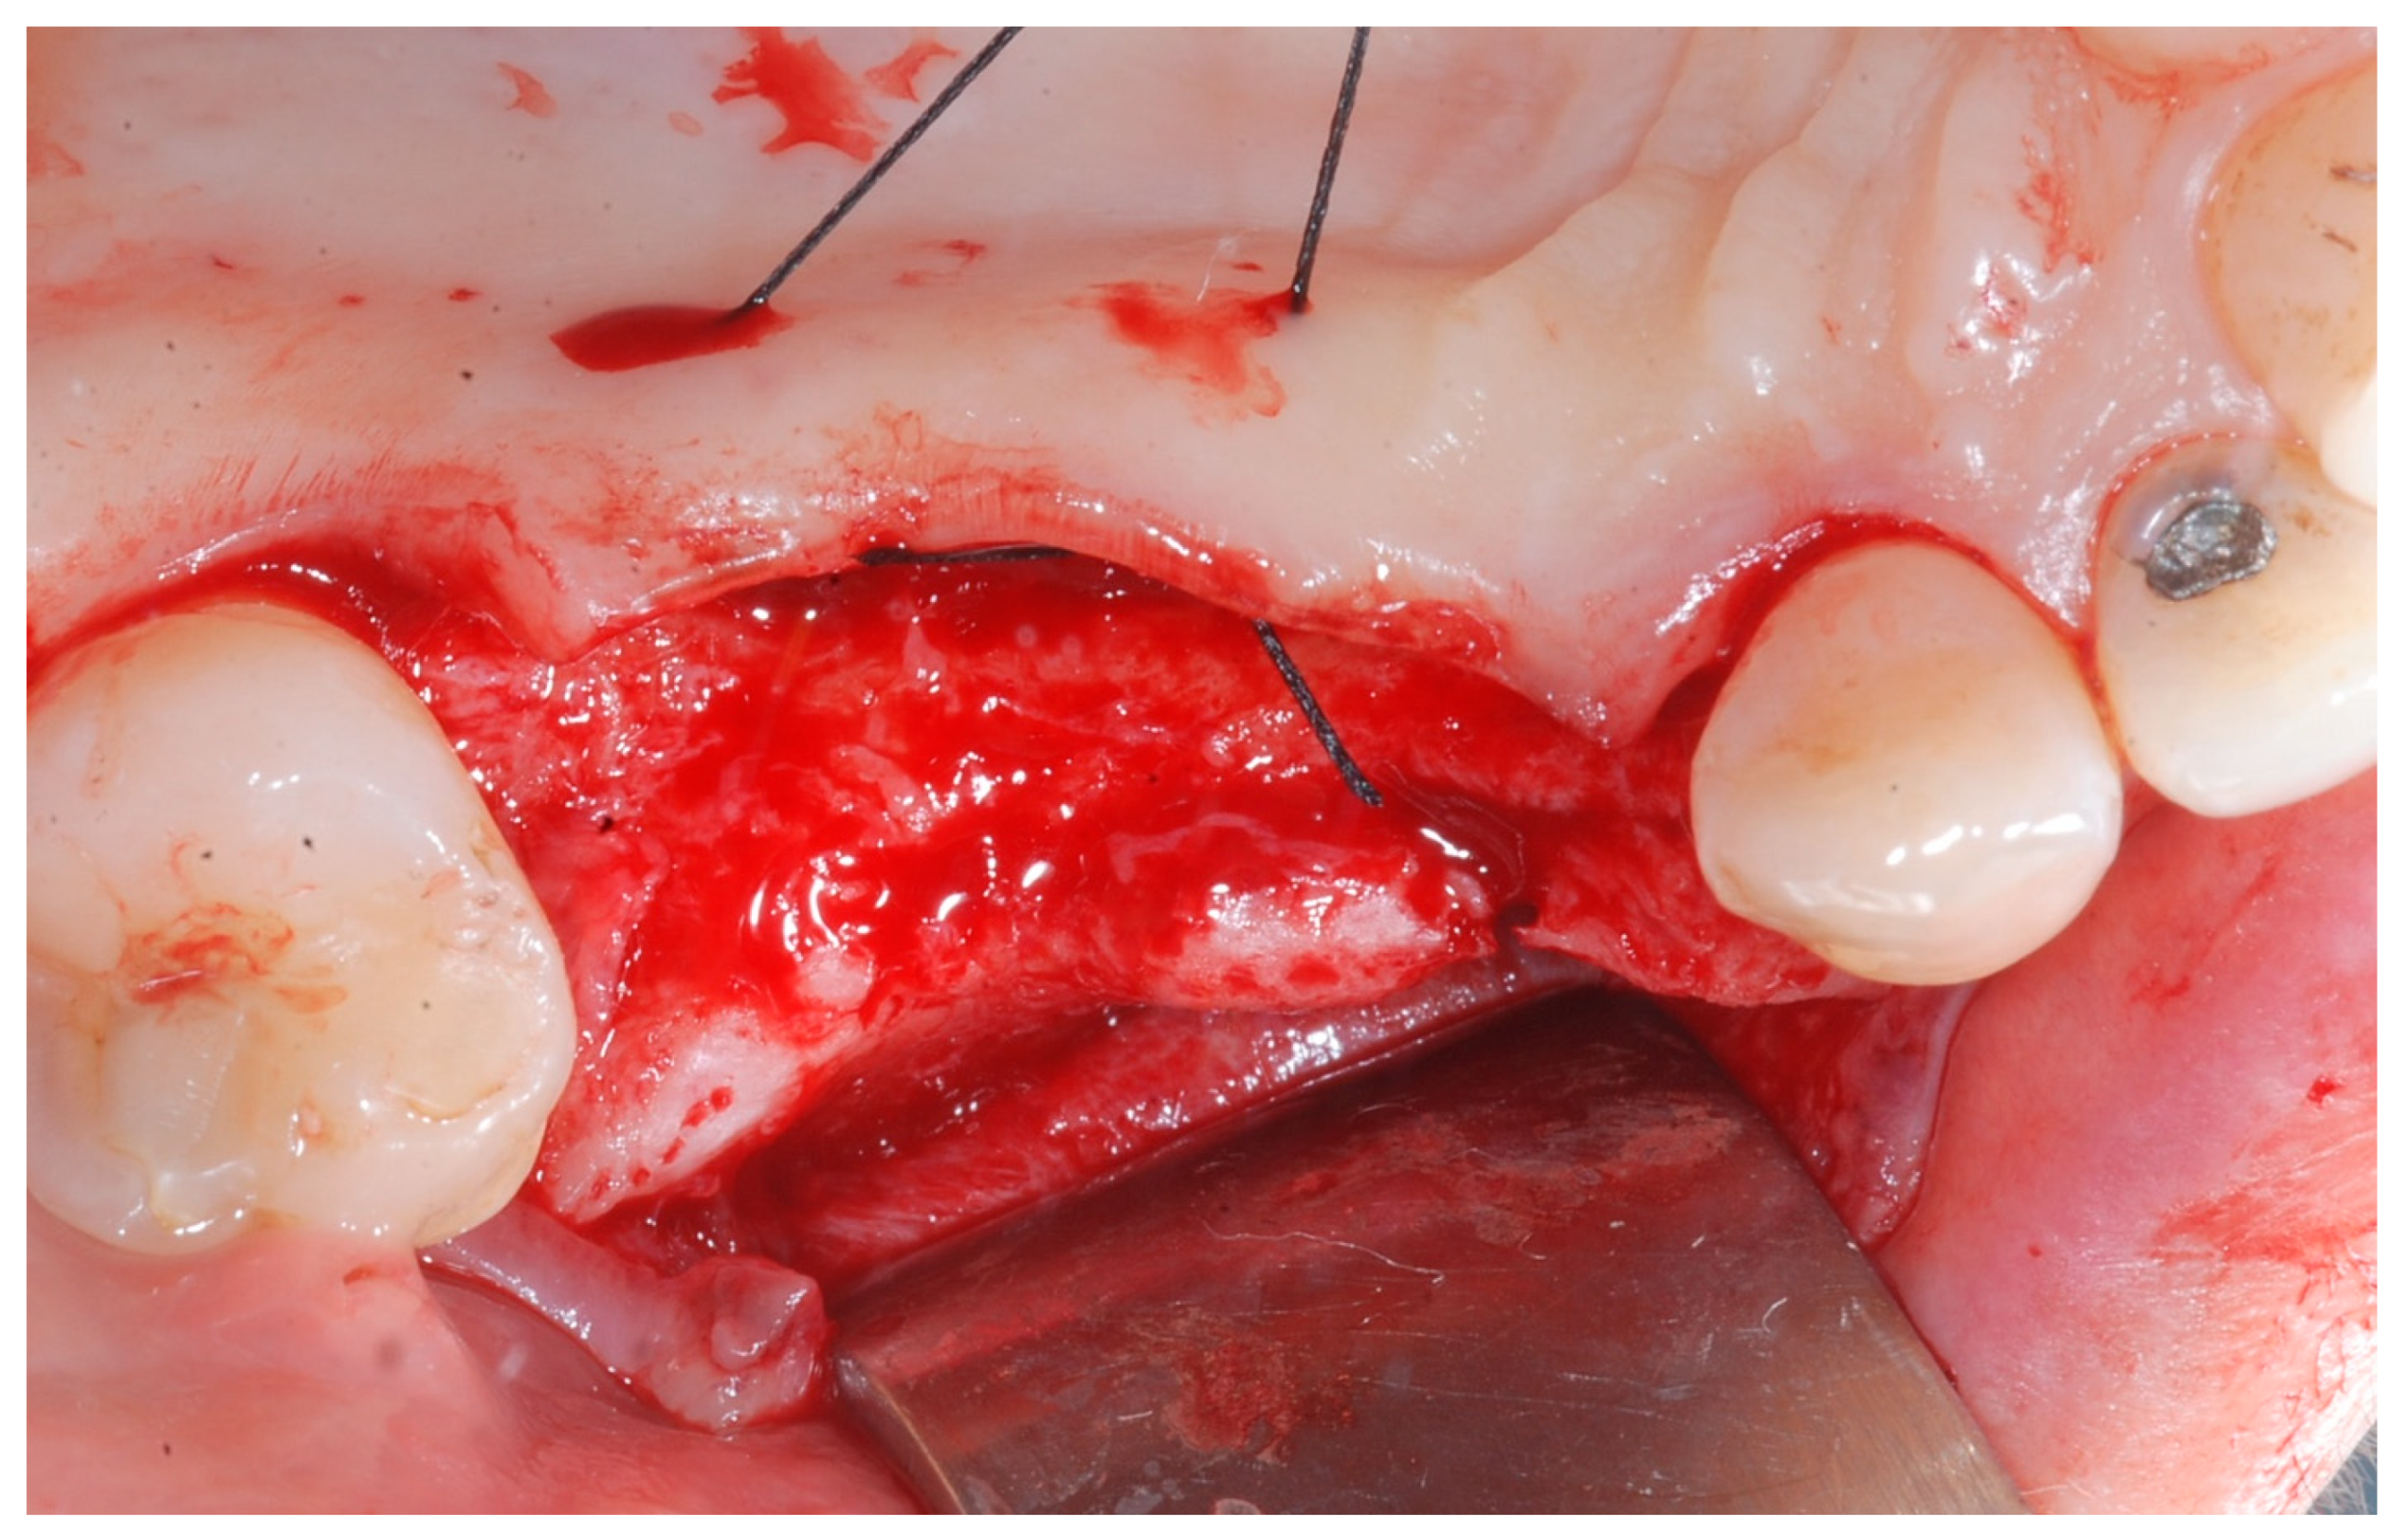

Six months following augmentation, re-entry surgery was carried out to uncover the implants and connect the healing abutments. Following chlorhexidine rinses and the injection of local anesthetics, crestal incisions as well as releasing incisions along the same lines as the ones during augmentation surgery were performed. Mucoperiosteal flaps were raised in order to visualize the augmented bone volume (Figure 9 and Figure 10).

During the 6-month period from T0 to T1, healing proceeded uneventfully in all patients, with no major complications or biocompatibility issues. No allergic reactions were observed. No complications such as flap dehiscence, membrane exposure, wound infection, fistulae with pus discharge, or foreign body reactions were noticed. None of the surgical sites had to be re-opened earlier. During the re-entry phase, in each surgical site no membrane remnants could be detected. Augmented newly formed hard tissue was observed clinically, with macroscopic features of healthy, bleeding, newly formed bone. Remnants of DBBM granules were occasionally visible and appeared firmly attached to the regenerated hard tissue, with no macroscopic signs of fibrous encapsulation. A thin layer of pseudo-periosteum with a thickness < 1 mm was seldomly observed. In all cases, implants appeared clinically stable, with no residual bony dehiscences or fenestrations at the buccal aspect.

Figure 9. Reopening surgery showing no membrane residues and obtained buccal bone thickness.

Medicina 61 01814 g009

Figure 10. Reopening surgery showing no membrane residues and obtained buccal bone thickness.

Medicina 61 01814 g010